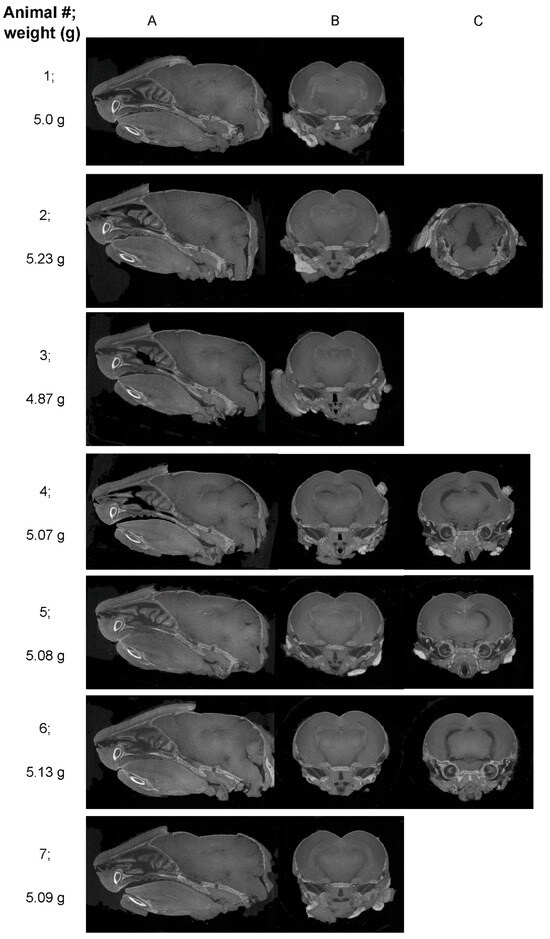

| Mouse ID | Reviewer 1 | Reviewer 2 | Reviewer 3 | Reviewer 4 |

|---|---|---|---|---|

| 1 | No pathological findings were noted | No pathological findings were noted | No pathological findings were noted | No pathological findings were noted |

| UI | UI | UI | UI | |

| 2 | Major gap at the rear of the brain | Asymmetrical gaps at the level of the hippocampus/thalamus | Asymmetrical, apparent volume loss in the hippocampus | Asymmetrical, increased space between the hippocampal region and thalamus and towards the hindbrain |

| ZIKV | ZIKV | ZIKV | ZIKV | |

| 3 | No pathological findings were noted | Some gaps, but no asymmetrical volume loss | No pathological findings were noted | Slight gaps between the hippocampal region and thalamus |

| probably UI | UI | UI | probably UI | |

| 4 | Multiple asymmetrical gaps penetrating across the midbrain | Clear asymmetrical gaps between structures, with the majority of abnormalities around the thalamus and hippocampus, continuing through the posterior brain | Very clear asymmetrical abnormalities, particularly at the level of the posterior hippocampus, and continuing more posteriorly | Gaps between hippocampus and cortex (right) and thalamus (left); Gap (right) appears to go through the majority of the brain |

| 5 | Maybe minor anomalies; | Asymmetrical gaps between the hippocampus and thalamus | Abnormality in the region anterior to nuc accumbens and at the level of striatum (less defined); Clear asymmetry at the level of the poster hippocampus; | Gap between the hippocampal region and the thalamus |

| UD | ZIKV | ZIKV | probably ZIKV | |

| 6 | Symmetrical gaps penetrating across images through the midbrain | Clear gaps at the hippocampus, continuing throughout the posterior brain | Very clear abnormalities, particularly at the level of the posterior hippocampus and extending posteriorly | Gap between the hippocampal region and thalamus on the left and right side, which runs through the majority of the brain |

| 7 | Maybe minor anomalies | Minor abnormalities | Some minor abnormality, which may be an imaging artifact or normal anatomical variation | Slight gap between the hippocampal region and thalamus; |

| UD | UI | UD | probably UI |